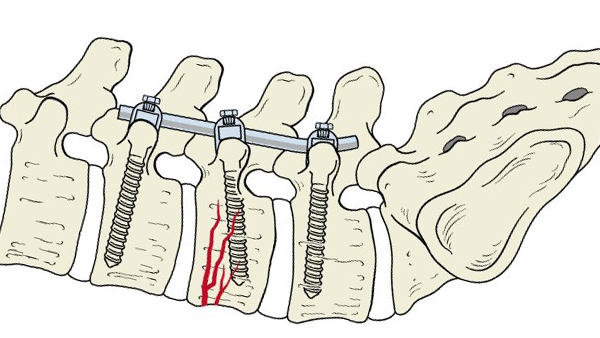

Транспедикулярная фиксация (ТПФ) применяется, когда вследствие физических, дистрофических и любых других изменений позвоночник оказывается не в состоянии полноценно выполнять свои опорные функции. Это могут быть переломы, деформации и смещения позвонков, онкозаболевания с поражением его отдельных участков и т.д. Перед проведением операции проводится индивидуальный подбор поддерживающей конструкции с учётом состояния пациента и наличия у него патологий. В ходе оперативного вмешательства хирург производит закрепление проволочного каркаса на сегментах позвоночника специальными винтами, которые вводятся в ножку позвонка (педикулу), что, к слову сказать, и дало название этому методу.

Надёжная фиксация позвонков и позвоночного столба при помощи высокопрочных титановых винтов позволяет значительно сократить период реабилитации пациента, ускорить процесс восстановления его трудоспособности.

В процессе операции происходит рассечение подкожной клетчатки в области проблемного участка и осуществляется доступ к позвонку. Далее происходит разметка: в соответствии со снимком при помощи штангенциркуля по обе стороны от остистого отростка определяются точки, которые вместе с известными точками введения винтов образуют траектории, по которым контролируется положение инструмента для формирования штифт-канала. Далее происходит сверление и непосредственное введение транспедикулярных винтов.